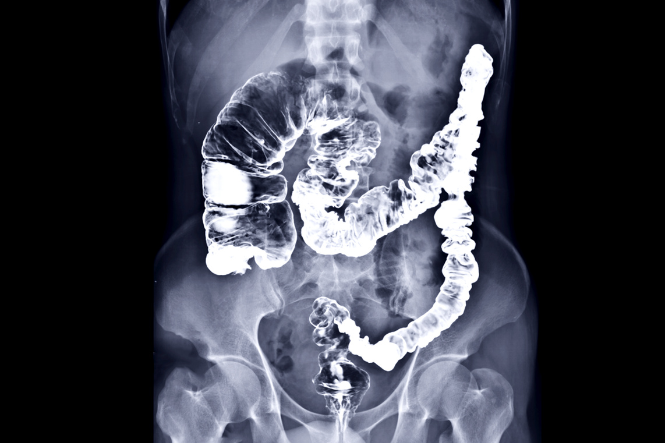

Digestive system – tests and procedures

A range of tests and procedures are used to check on your digestive health and to diagnose and monitor any digestive system condition you may have. Find out about these tests and procedures here.